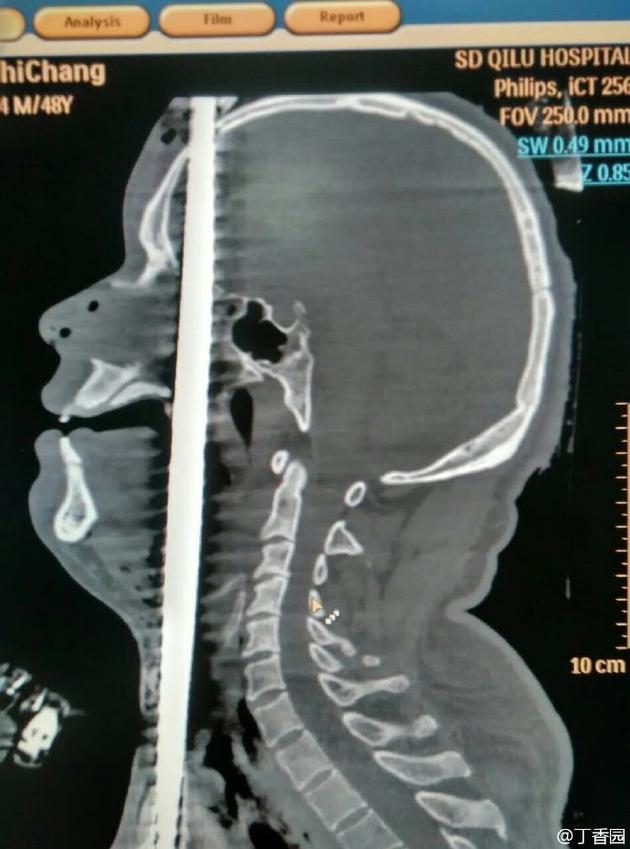

螺纹钢筋在头部

本报讯 6月14日下午4点,山东大学齐鲁医院急诊收治了一名正中贯通伤患者,该患者高空作业时从5米高空坠落,地上正好有一竖起的钢筋,钢筋从男子的阴部直穿头顶。经过7个多小时的手术,钢筋被顺利取出,测量长度约150厘米。

经检查发现,该男子意识清楚,鼻腔口腔有鲜血流出。钢筋从男子的右阴囊插入,途经泌尿系统,伤及腹部的肝脾,紧贴心脏和颈动脉贯穿而过。从咽喉直插入口腔,舌头,上颚经鼻腔,插入大脑,最后钢筋从头顶穿出。